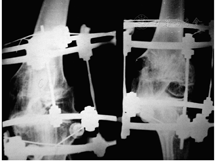

环式外固定器于1951年由Ilizarov发明,并使用其治疗骨不连、骨缺损,他偶然在临床工作中发现缓慢牵拉促进骨再生的现象(图2),进行了动物实验并获得证实。后期采用超大样本的动物实验(一期实验采用480条犬),于20世纪70年代提出了"张力应力法则"生物学理论,即给活体组织持续、稳定、缓慢的牵拉,使其产生一定张力,可刺激某些组织的再生和活跃生长,牵拉组织再生需要血液循环[4]。基于这一理论,Ilizarov发明和改进了一系列肢体延长的环形外固定器械,使得牵拉成骨技术(distraction osteogenesis,DO)在理论和技术层面都得到了重大突破[5]。

在此后的几十年间,该技术被广泛传播,其应用范围也随着研究的深入而逐渐扩大。如今,牵拉技术已不仅局限于骨的再生,越来越多的研究发现牵拉力学刺激下的血管、神经、肌腱、肌肉、皮肤等软组织均可发生再生现象(图3),此技术被归纳为牵拉成组织术(distraction histogenesis, DH)。因此,牵拉成组织技术的范畴较牵拉成骨更广,实际上反映了在张力应力法则下,牵拉技术所带来的"骨与软组织同步再生"[6]。